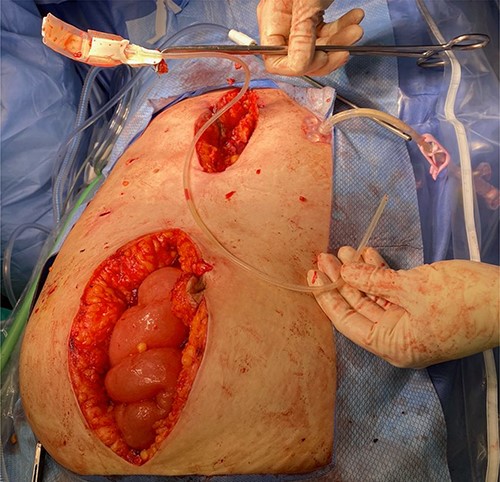

The patient is a 54-year-old woman with locked-in syndrome, which is complete paralysis of all voluntary muscles excluding those that control ocular movements, secondary to Guillain–Barré Syndrome (GBS) who had a laparoscopic adjustable gastric band placed in 2008. A few months prior to her presentation to the emergency department, the subcutaneous port of the band was removed by her care team without consultation from a surgery team, as the skin site appeared to be infected. Of note, the tubing was left in situ. The patient presented to the emergency department with generalized abdominal discomfort for 1 week associated with fevers noted by her caregivers. Upon admission, she was resuscitated and treated with broad-spectrum intravenous antibiotics. A computerized tomography scan of the abdomen and pelvis revealed a pelvic abscess around the tip of the gastric band tubing (Fig. 1). She did not improve after 5 days of medical management; therefore, the patient was consented for surgical removal of the gastric band and tubing.

Diagnostic laparoscopy was initially carried out in hopes of identifying and removing the gastric band. However, adequate pneumoperitoneum was difficult to achieve due to minimal response to paralytic agents with increasing dosages presumably secondary to the patient’s underlying disease. As such, the decision was made to convert to laparotomy. A lower midline incision was made. The gastric band tubing was noted coursing over the ascending colon. This was traced down into the pelvis and an abscess cavity containing a large amount of purulent fluid was encountered. A swab of the fluid was sent for culture and sensitivity and the fluid, and it was then carefully suctioned and irrigated. In order to remove the gastric band, a separate upper midline laparotomy incision was made. Careful dissection was carried out until we were around the gastric band; its anchoring sutures were cut, and the band was freed from around the stomach. Interestingly, the band itself appeared to be infected and had a foul odor. The band along with the tubing was removed from the surgical field (Fig. 2). A Jackson–Pratt drain was placed in the pelvis to facilitate further drainage post-operatively. The patient tolerated the procedure well, her gastrostomy tube feeds were restarted on POD 1 and she had an uneventful recovery.